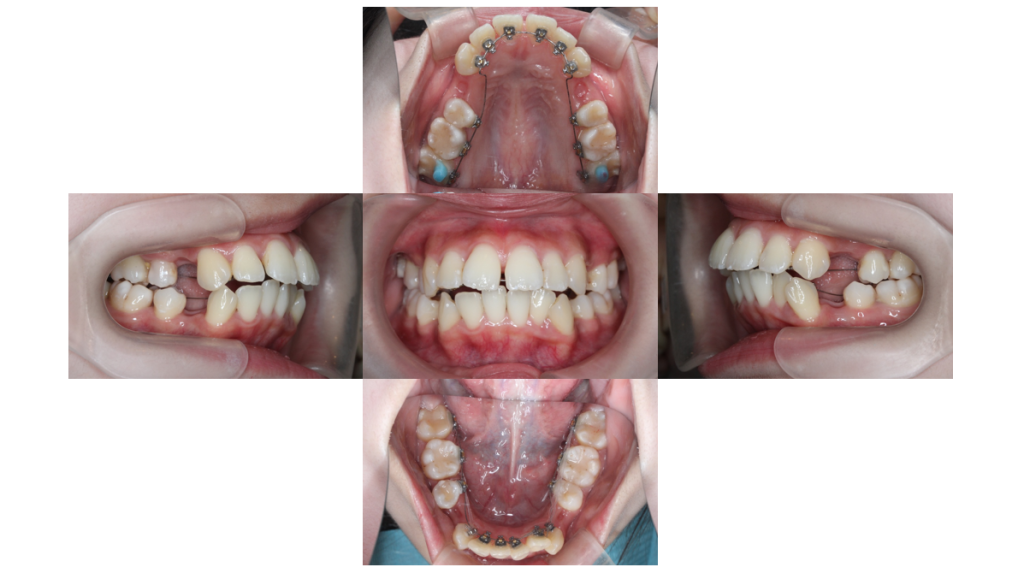

初診

叢生・裏側矯正の症例治療開始前の口腔内写真です。